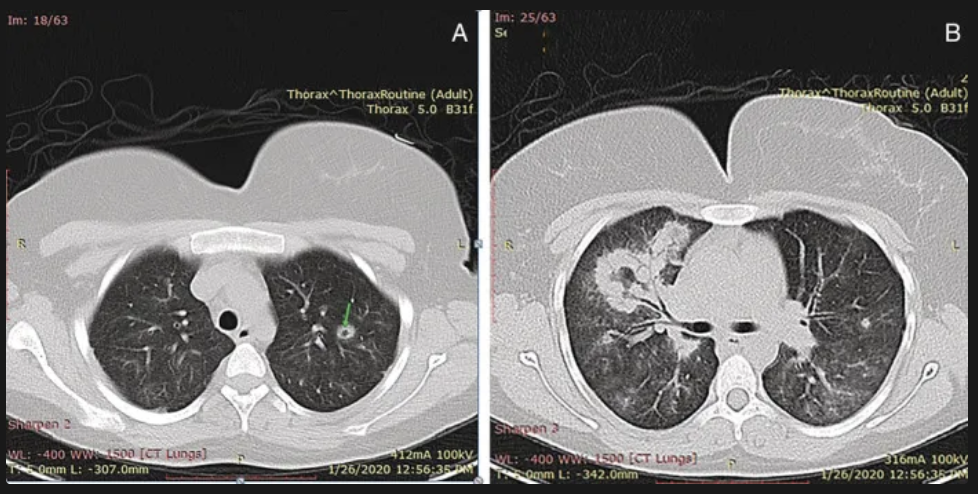

Dx de la granulomatosis con poliangitis de wegener?

Rx de torax:

nódulos e infiltrado pesistentes, a veces cavidades

Biopsia de tejido afectado:

Inflamación de vasos pequeños (vasculitis), granulomas caseosos

Biopsia renal:

Glomerulonefritis segmentaria necrotizante sin depósitos inmunitarios .